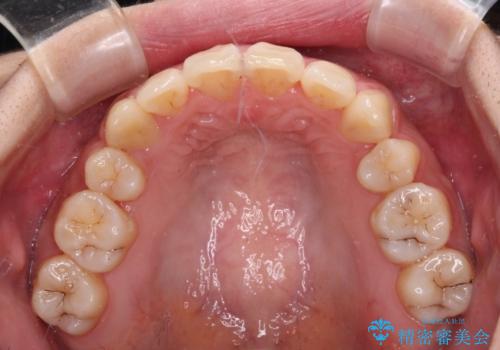

元々奥歯に負担のかかる咬み合わせですり減っていたため、仕上がった歯並びでも奥歯が咬んでいないように見えましたが、実際にはしっかりと咬合しており、患者様本人も咬んだ感触に違和感はないとのことでした。